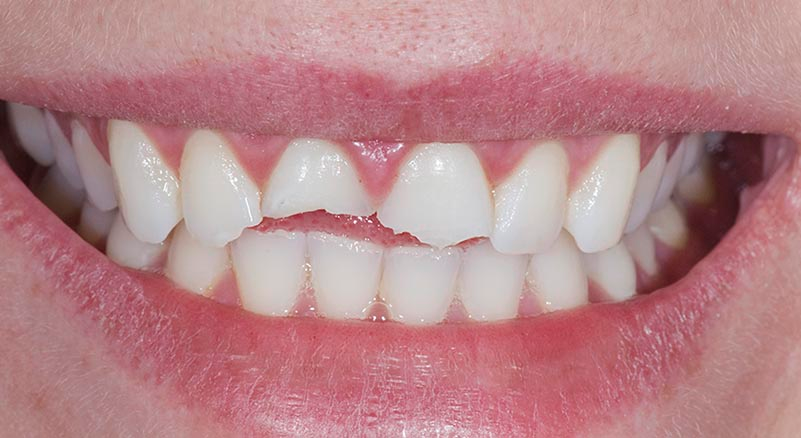

Kıymetli Hastamız! Kliniğimizde cerrahi işlemler dışında diş beyazlatma, porselen kaplama, gülüş tasarımı, tedavi (diş dolgusu, kanal tedavisi), hareketli (total ve parsiyel protezler), hibrid (implantüstü) ve sabit protezler (porselen, zirkon, lamina) ile temel dişeti hastalığı tedavilerini (diş taşı temizliği, küretaj) de yapmaktayız. Sağlıklı günler dileğiyle!